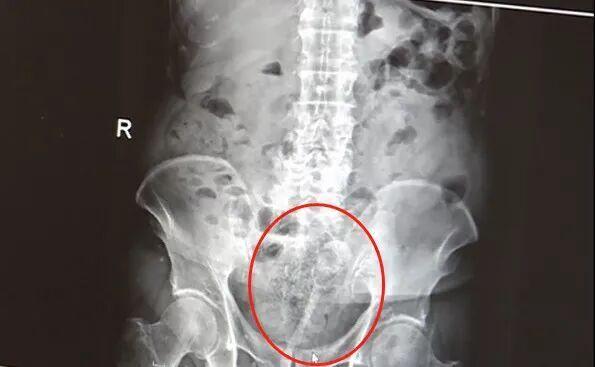

老人用筷子通便被120拉走,这事儿听起来就离谱,但现实中还真发生了。有82岁的王伯,清晨被老伴发现瘫坐在卫生间地上,浅色裤衩被鲜血浸透,马桶里还浮着半截沾血竹筷。送到医院时,他血压骤降、意识模糊,直肠粘膜被捅破,出血接近失血性休克临界值。还有85岁的陈大爷,用筷子辅助排便后肛周和腹部剧痛,发热、流脓液,到医院一查直肠上段穿孔,盆腔大面积感染。便秘痛苦可以理解,但用筷子这种危险方式真不可取,有问题还是得及时就医。